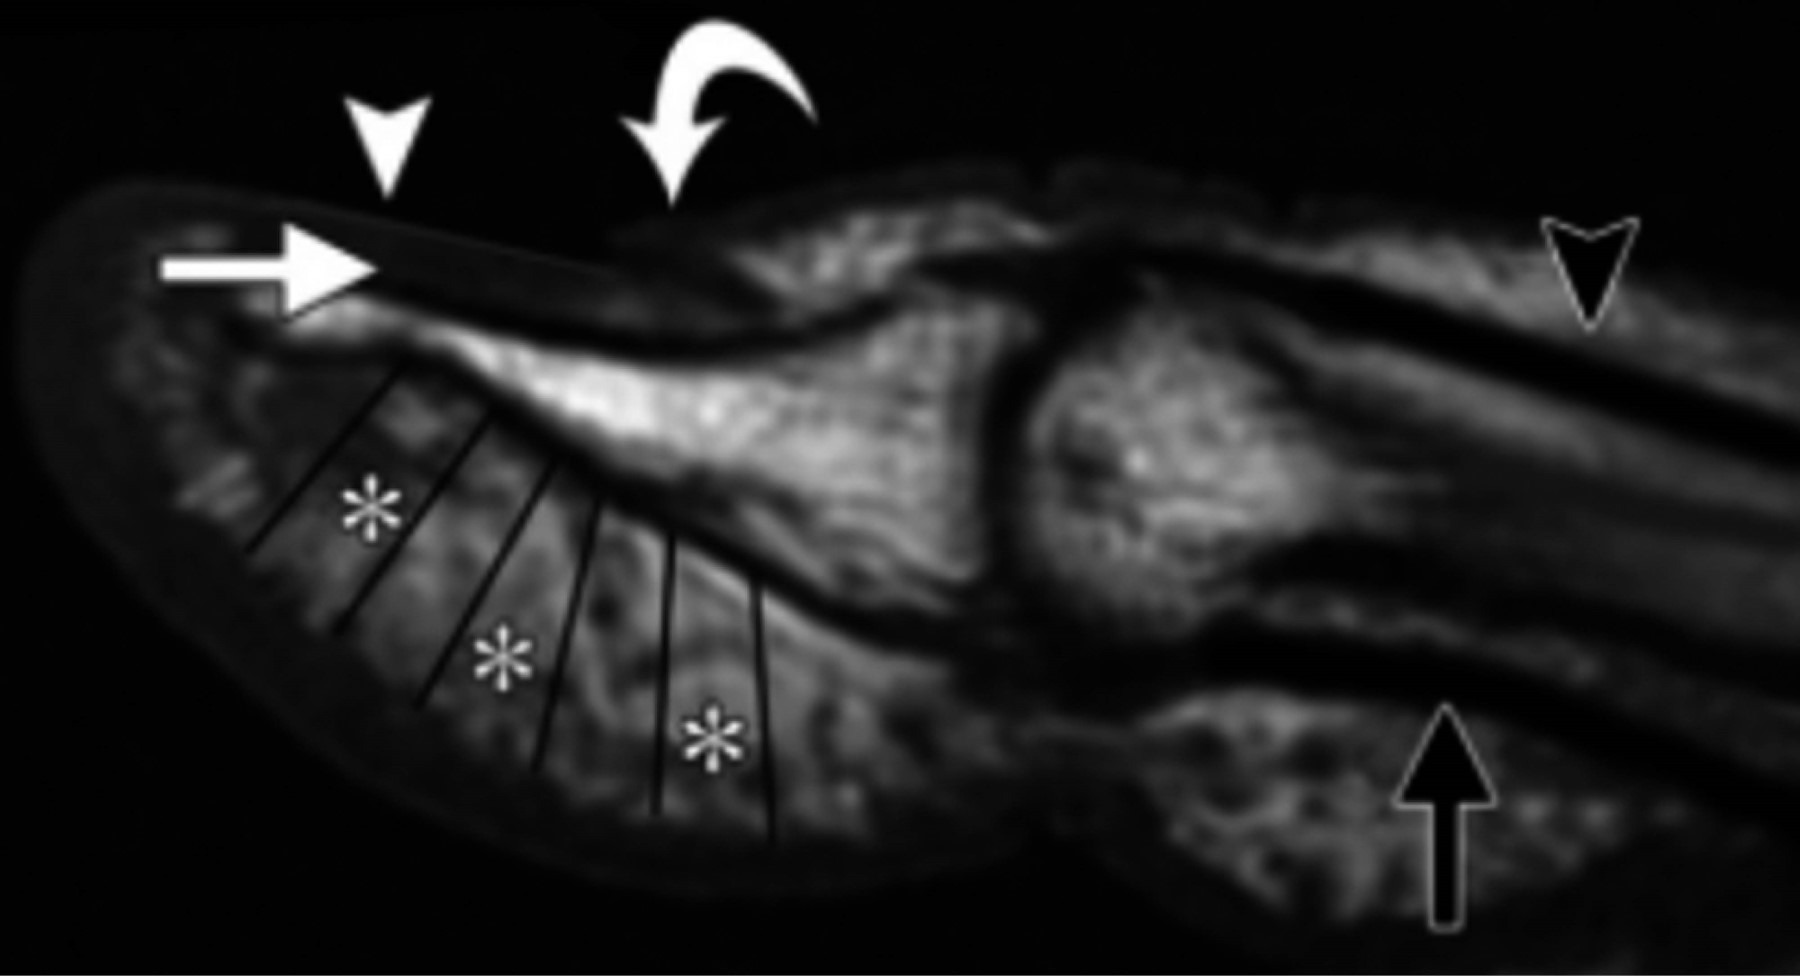

Figure 1

Figure 2

Figure 3

Figure 4

Figure 5

Figure 6